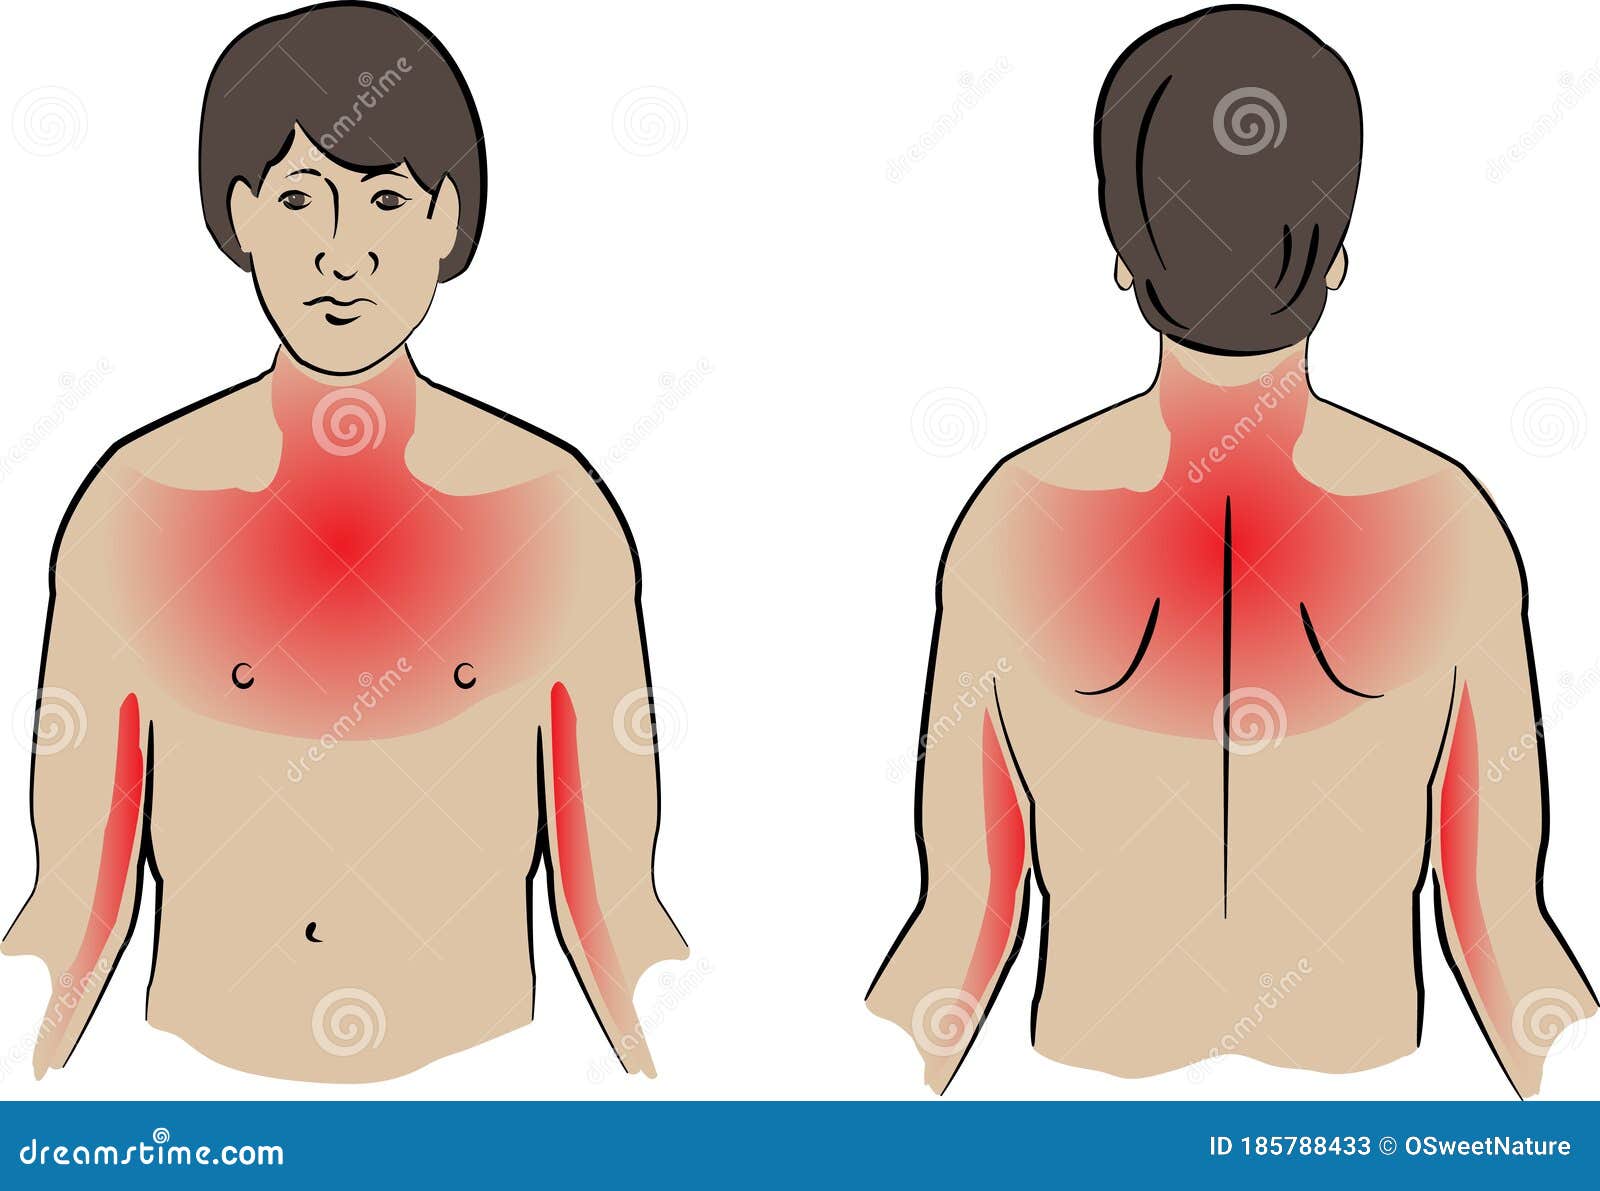

What Are Men s Symptoms Of A Heart Attack Warning Signs In Men

Heart Attack Pain Locations Medical Illustration Royalty Free Stock